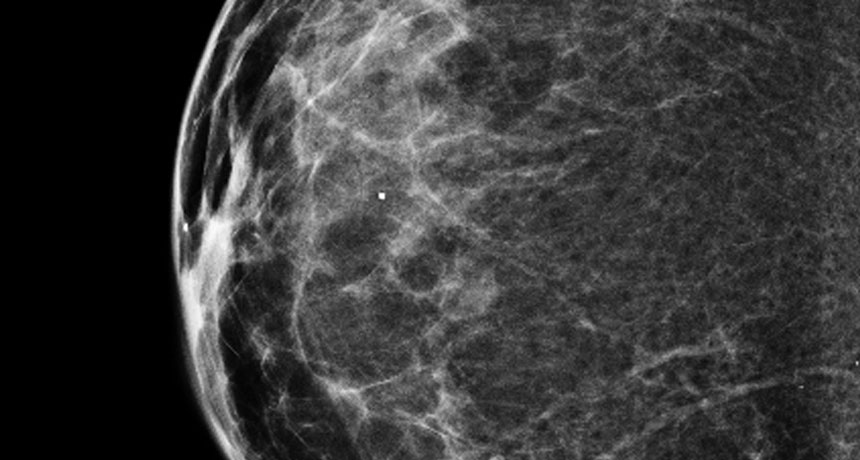

ALL CLEAR  This 3-D mammogram shows a normal breast. Initial studies suggest that the technology is more sensitive than traditional 2-D imaging, but it’s unclear if that helps reduce the number of deaths from breast cancer.

National Cancer Institute, National Institutes of Health/Flickr (CC BY-NC 2.0)